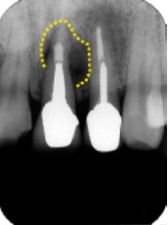

デンタルX線診査

左上中切歯根尖側に骨透過像

深い歯周ポケットと大きな透過透像より歯根破折と診断